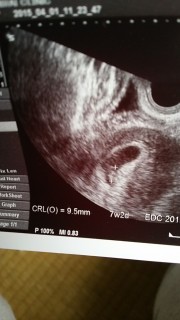

写真:7w2d:らららんどさん

診察当初の妊娠週数は8w2dですが、赤ちゃんが7w2dの大きさでしたので、こちらに投稿させていただきました。心拍確認でき、3人目でもやっぱり嬉しいし感動します。先生に『少し小さめだねぇ』と言われ心配になり『持ちます?』と聞いたら『持つ持つ』と(笑)診察後、即座に母子手帳を申請に。2週間後は頭、体、手も確認できますように。CRL=9.5mm